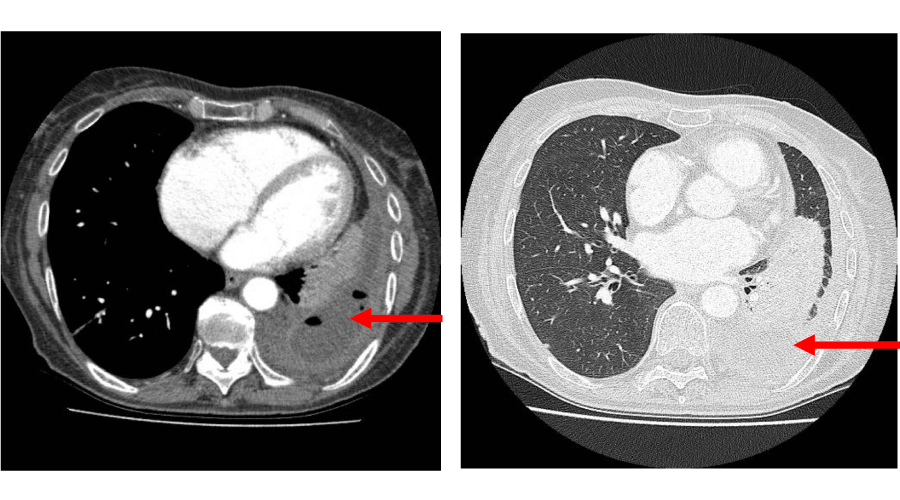

A review of the thoracic surgical database identified 75 patients who had undergone VATS drainage in the management of post-pneumonic empyema between May 2007 and May 2011. Patients requiring open drainage with rib resection, thoracoplasty or flap reconstruction were excluded from this study. Patients with an underlying thoracic malignancy were also excluded. The most common presenting symptoms were shortness of breath, fever and cough and were reported in 35-40% of cases. Others seen less frequently included chest pain, loss of appetite, loss of weight and haemoptysis. All patients had been resistant to medical treatment which varied from antibiotic therapy only, to pleural aspiration or drain insertion. The cohort was divided into those patients managed conservatively for less than two weeks prior to surgery (Group I n=34) and those managed for 2 weeks or more (Group II n=41). Diagnosis in both groups was confirmed using CT scan of the chest (Figure 1), with or without analysis of pleural fluid.

Figure 1: